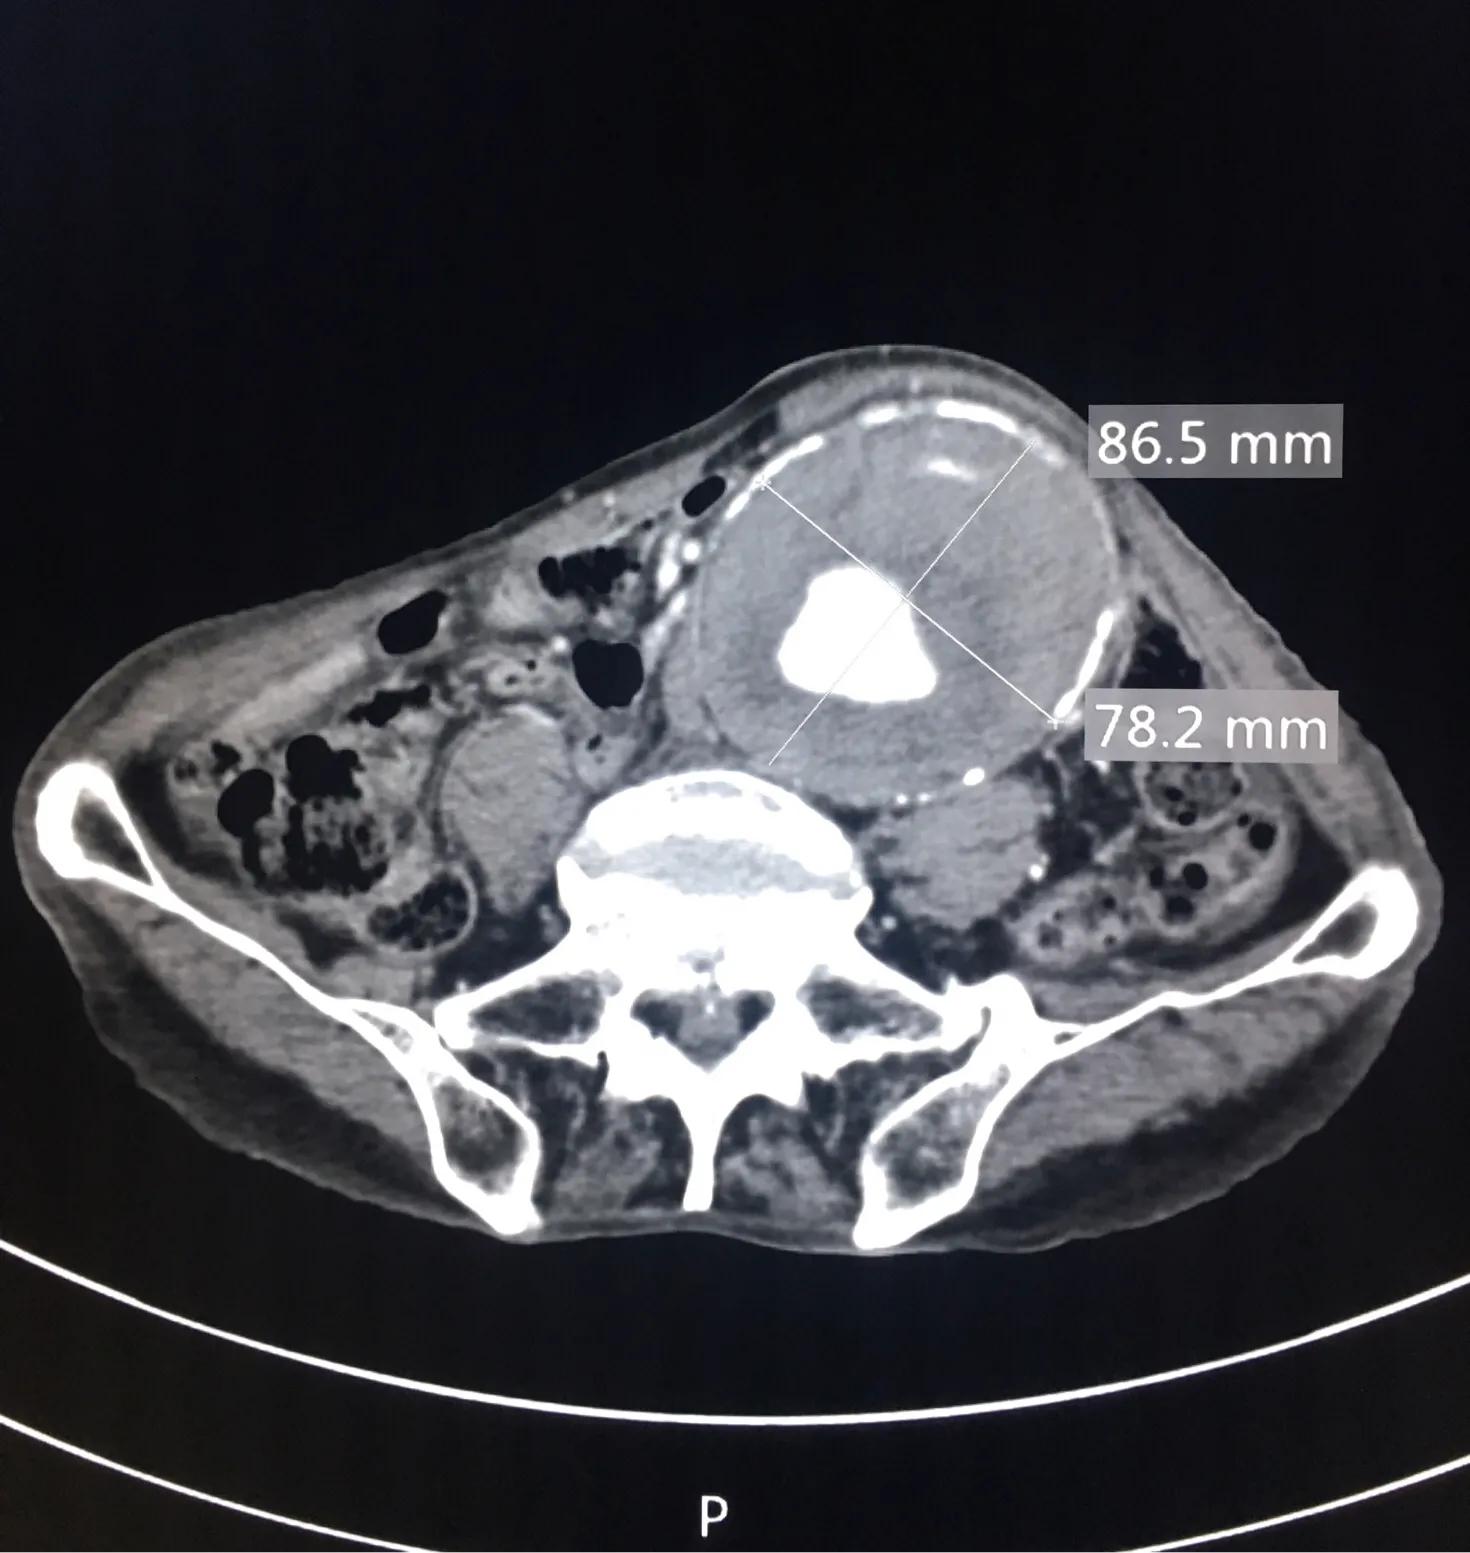

腹部CT明确,腹主动脉瘤样扩张,范围较大,最大横径接近快10厘米了,管壁可见不强化的血栓形成,诊断腹主动脉瘤。

- 真性动脉瘤主动脉局限性扩张或膨凸,附壁血栓表现为新月形或环形充盈缺损